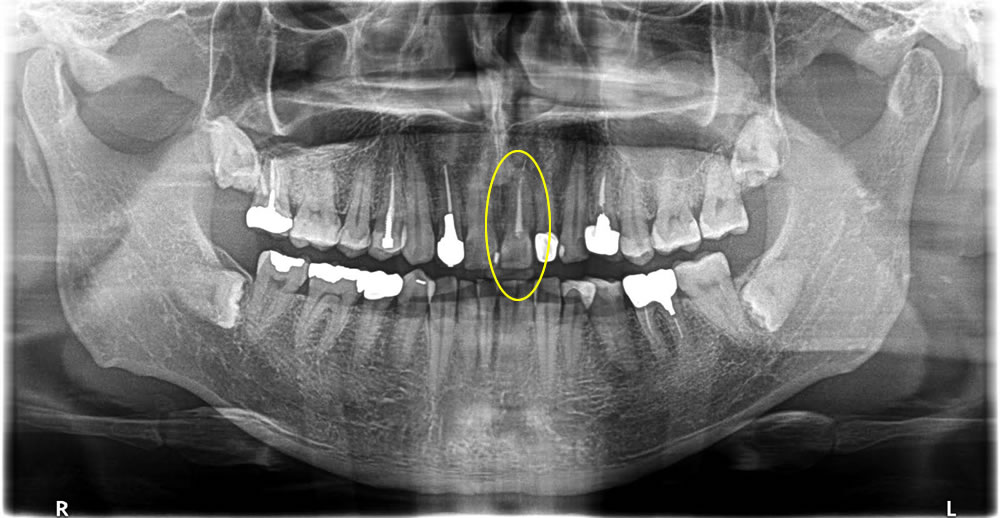

痛みのあるブリッジの歯をインプラントで治療した症例

年齢

50代

性別

女性

症例を見る